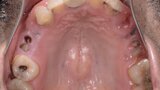

Fig. 2: Pre-op maxillary occlusal view.